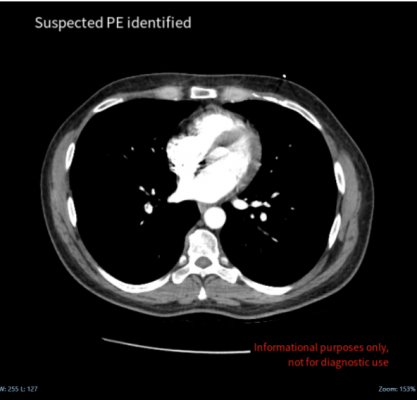

Pulmonary embolism is the blockage of an artery in the lungs and is one of the major causes of death, morbidity and hospitalization worldwide. It is difficult to diagnose PE as it manifests in diverse ways and can be mimicked by a range of other conditions. Cina Chest provides rapid automatic PE detection on CT chest angiography, providing clinicians with accurate and rapid real-time alerts on the disease.